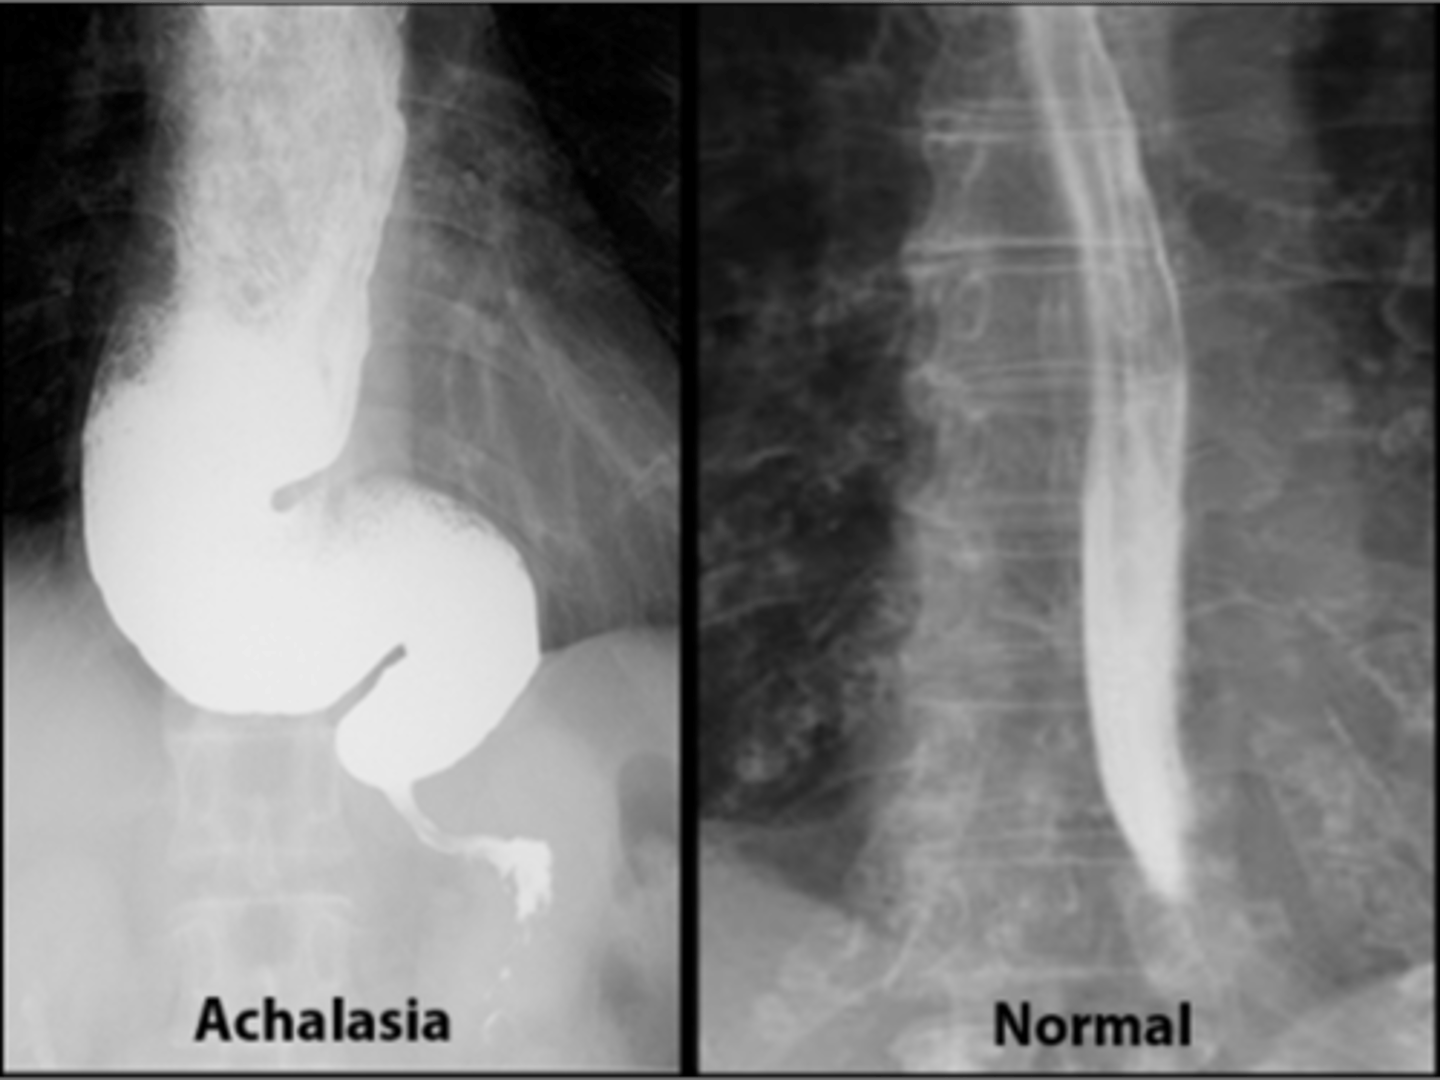

Achalasia

Achalasia (pic 5)

Achalasia (pic 2)

Achalasia (pic 3)

Achalasia (pic4 )